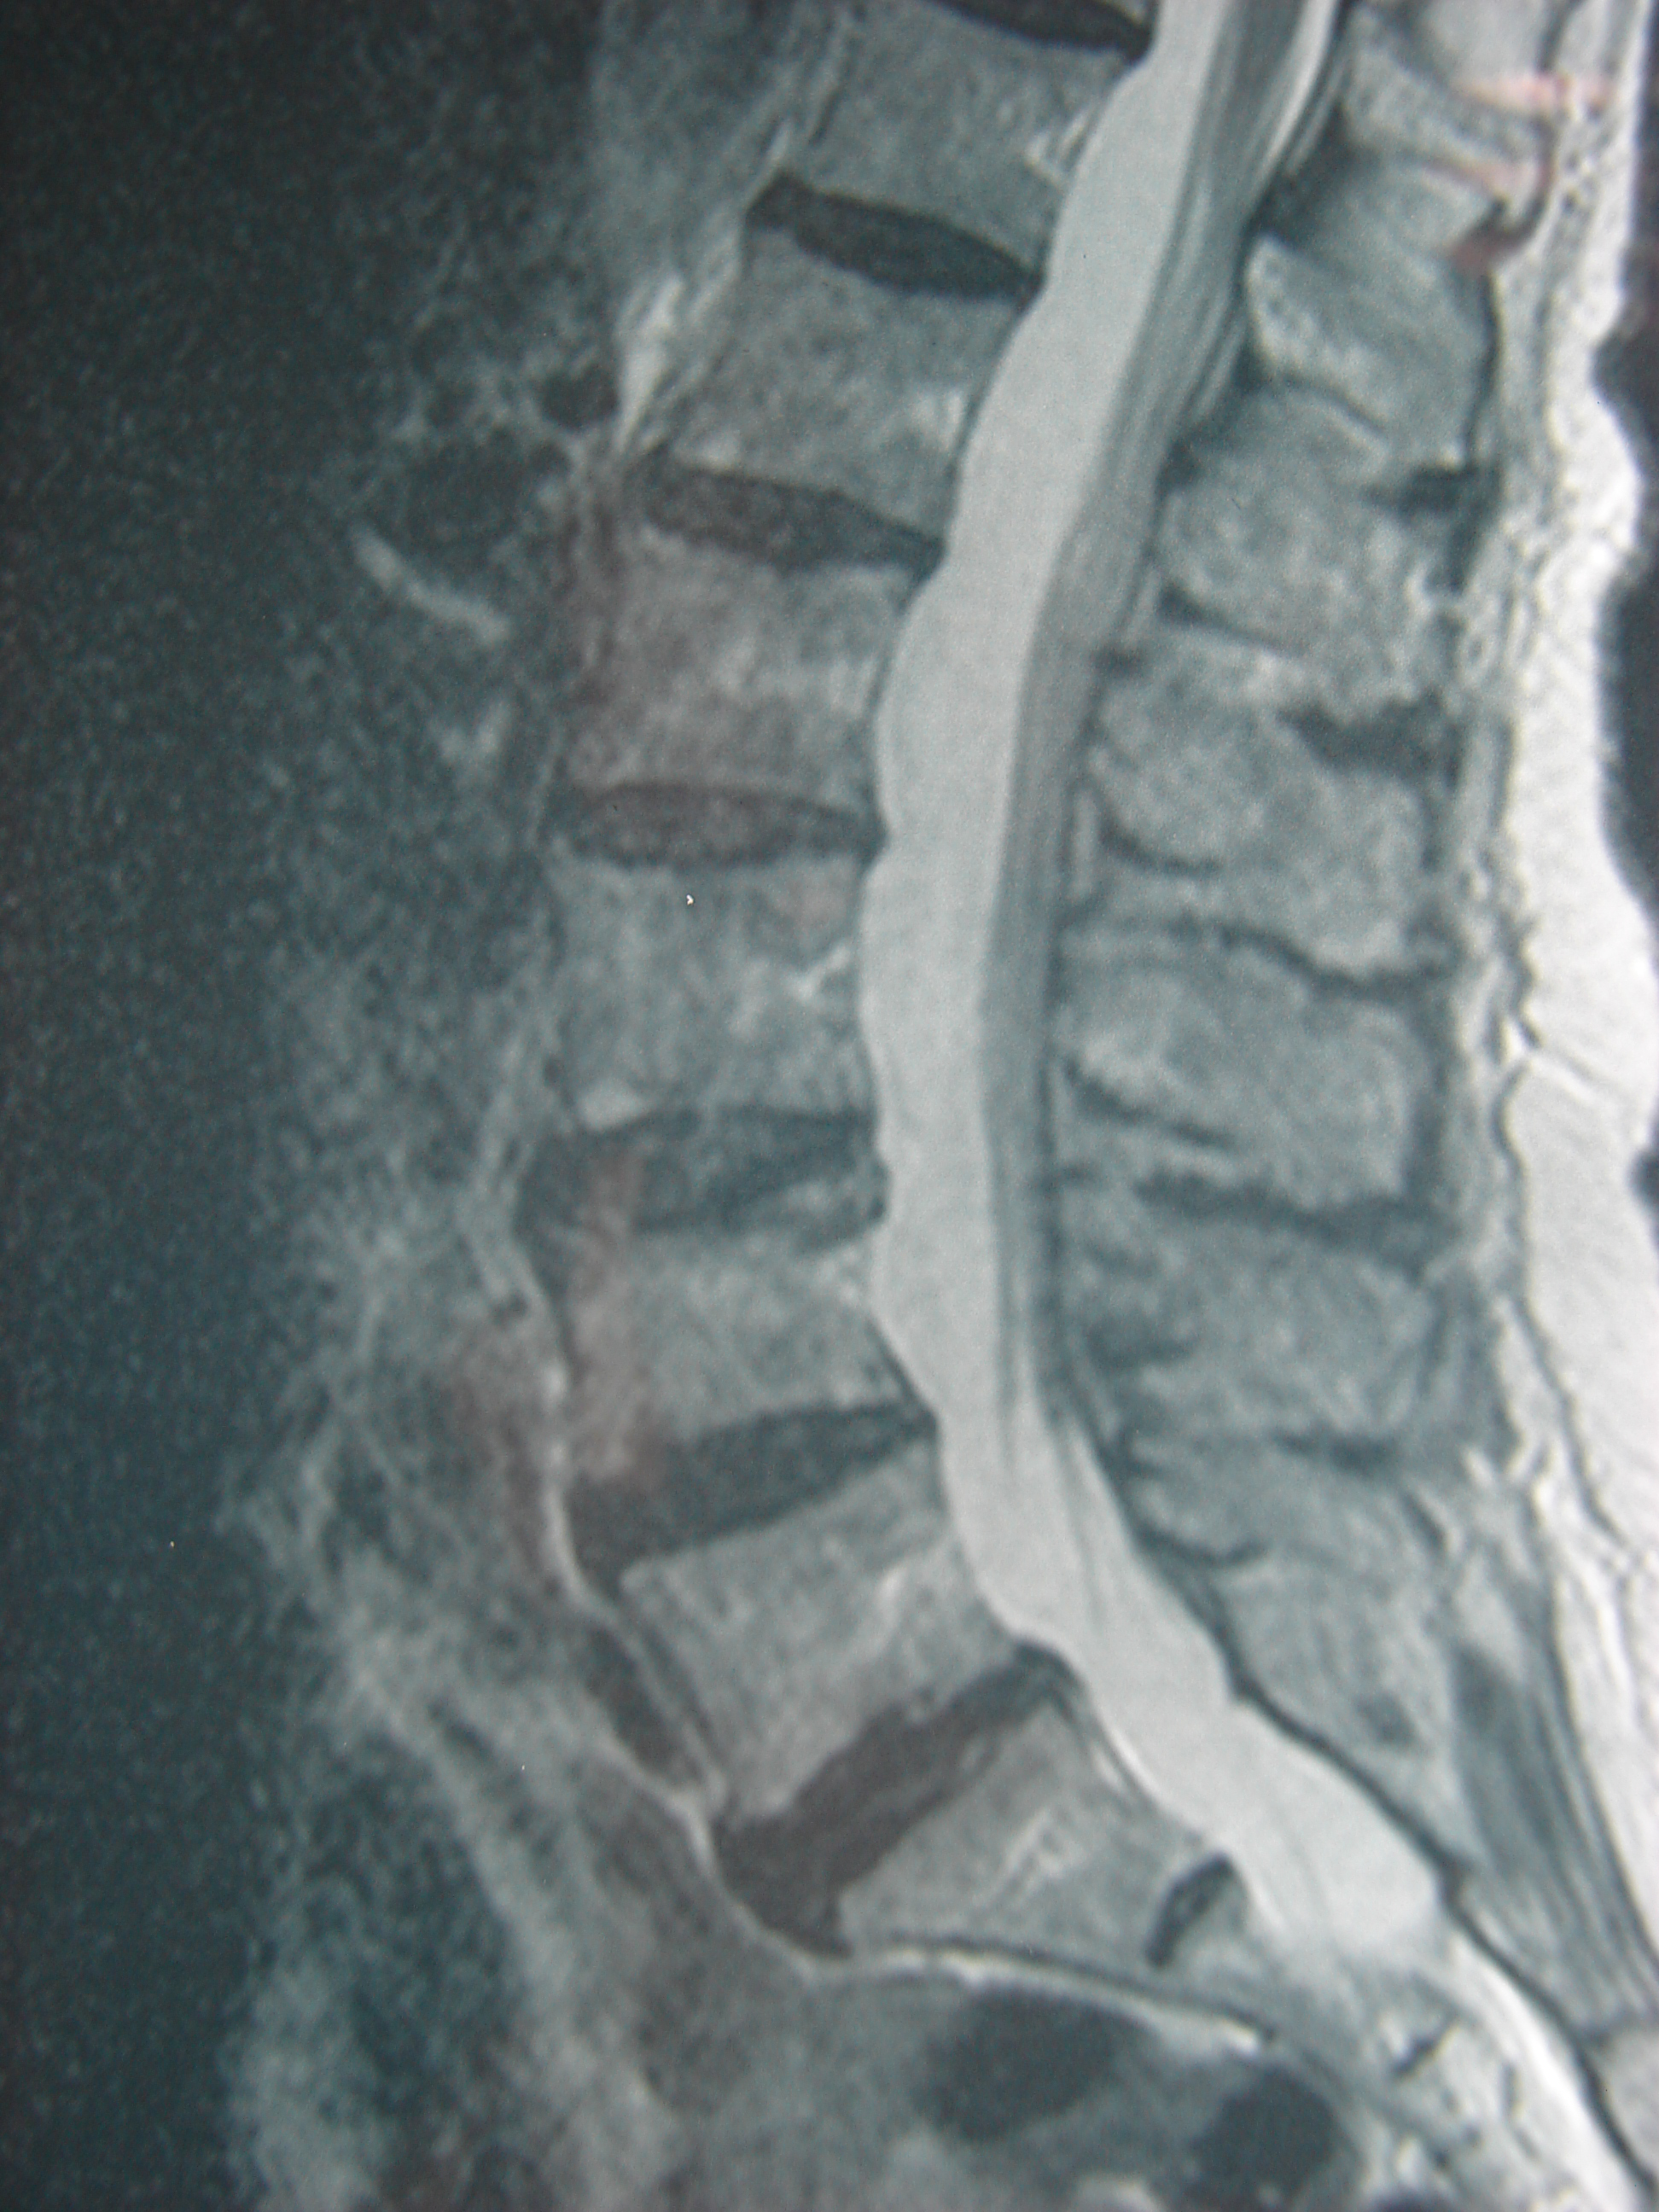

Εικ 1: α,β,γ,δ Μαγνητική Τομογραφία της Θωρακικής Μοίρας και ε της Οσφυικής Μοίρας της Σπονδυλικής Στήλης (Ακολουθία Τ1-Τ2).

Παρατηρείται η ύπαρξη μικρού βαθμού συμπιεστικό κάταγμα του 8ου θωρακικού σπονδύλου

Η κα Μ.Π., κατόπιν πτώσεως από χαμηλό ύψος, υπέστη κάκωση στη Θωρακική Μοίρα της Σπονδυλικής Στήλης. Ο γενόμενος τότε έλεγχος της περιοχής δια μαγνητικής τομογραφίας, έδειξε την ύπαρξη συμπιεστικού κατάγματος του 8ου Θωρακικού Σπονδύλου, με μικρή απώλεια ύψους, όπως επίσης και την ύπαρξη εσωτερικής κάκωσης του 7ου θωρακικού σπονδύλου (οστικό οίδημα) χωρίς απώλεια ύψους.